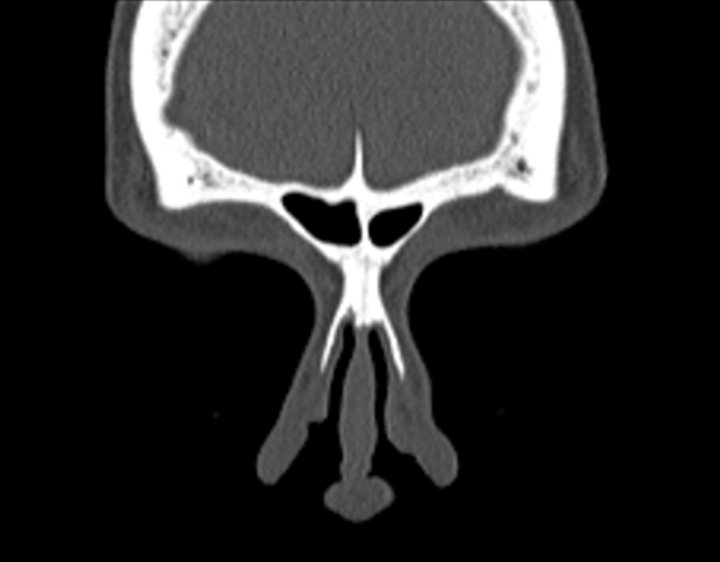

Click any image for labels.